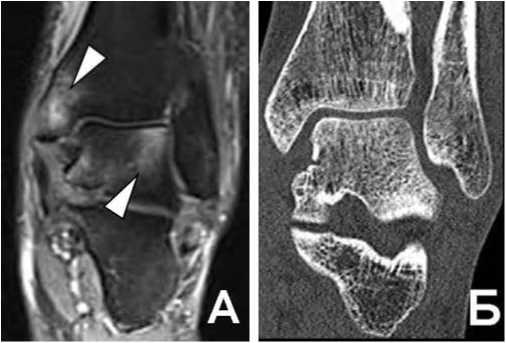

Рис. 8. Т1 TSE Томограммы в коронарной проекции пациента с жалобами на боль в голеностопном суставе без анамнеза острой травмы.

А: В своде блока таранной кости определяется участок формирования костного фрагмента, покрытый суставным хрящом (обычная стрелка).

Б: Тот же пациент, через 1 месяц. Отмечается перелом суставного хряща в Медиальном отделе, нестабильность фрагмента с небольшим смещением (треугольная стрелка).

Остеохондральные повреждения голеностопного сустава часто выявляются в своде блока таранной кости, могут сочетаться с разрывом коллатеральных связок (рис. 8). Berndt и Harty классифицировали остеохондральные повреждения блока таранной кости на 4 стадии на основе целостности суставного хряща и состояния субхондрального фрагмента [6].

По существу МРТ является единственным методом, дающим исчерпывающую информацию о размере и локализации повреждения, состоянии покровного суставного хряща, конгруэнтности суставных поверхностей, жизнеспособности костного фрагмента, стабильности: или степени восстановления между остеохондральным фрагментом и местом-донором, локализации костного фрагмента при его смещении в полость сустава [7].